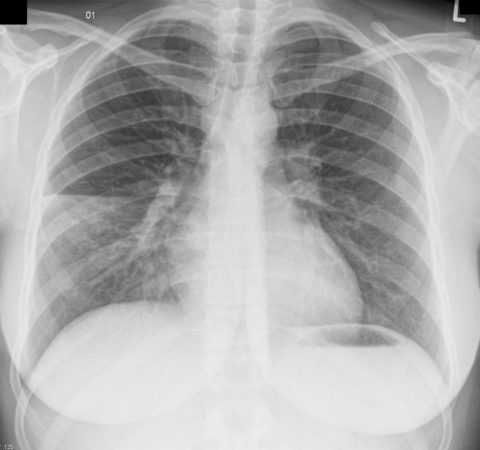

- инфекция (пневмония, воспаление мочевыделительной системы или пищеварительной трубки),